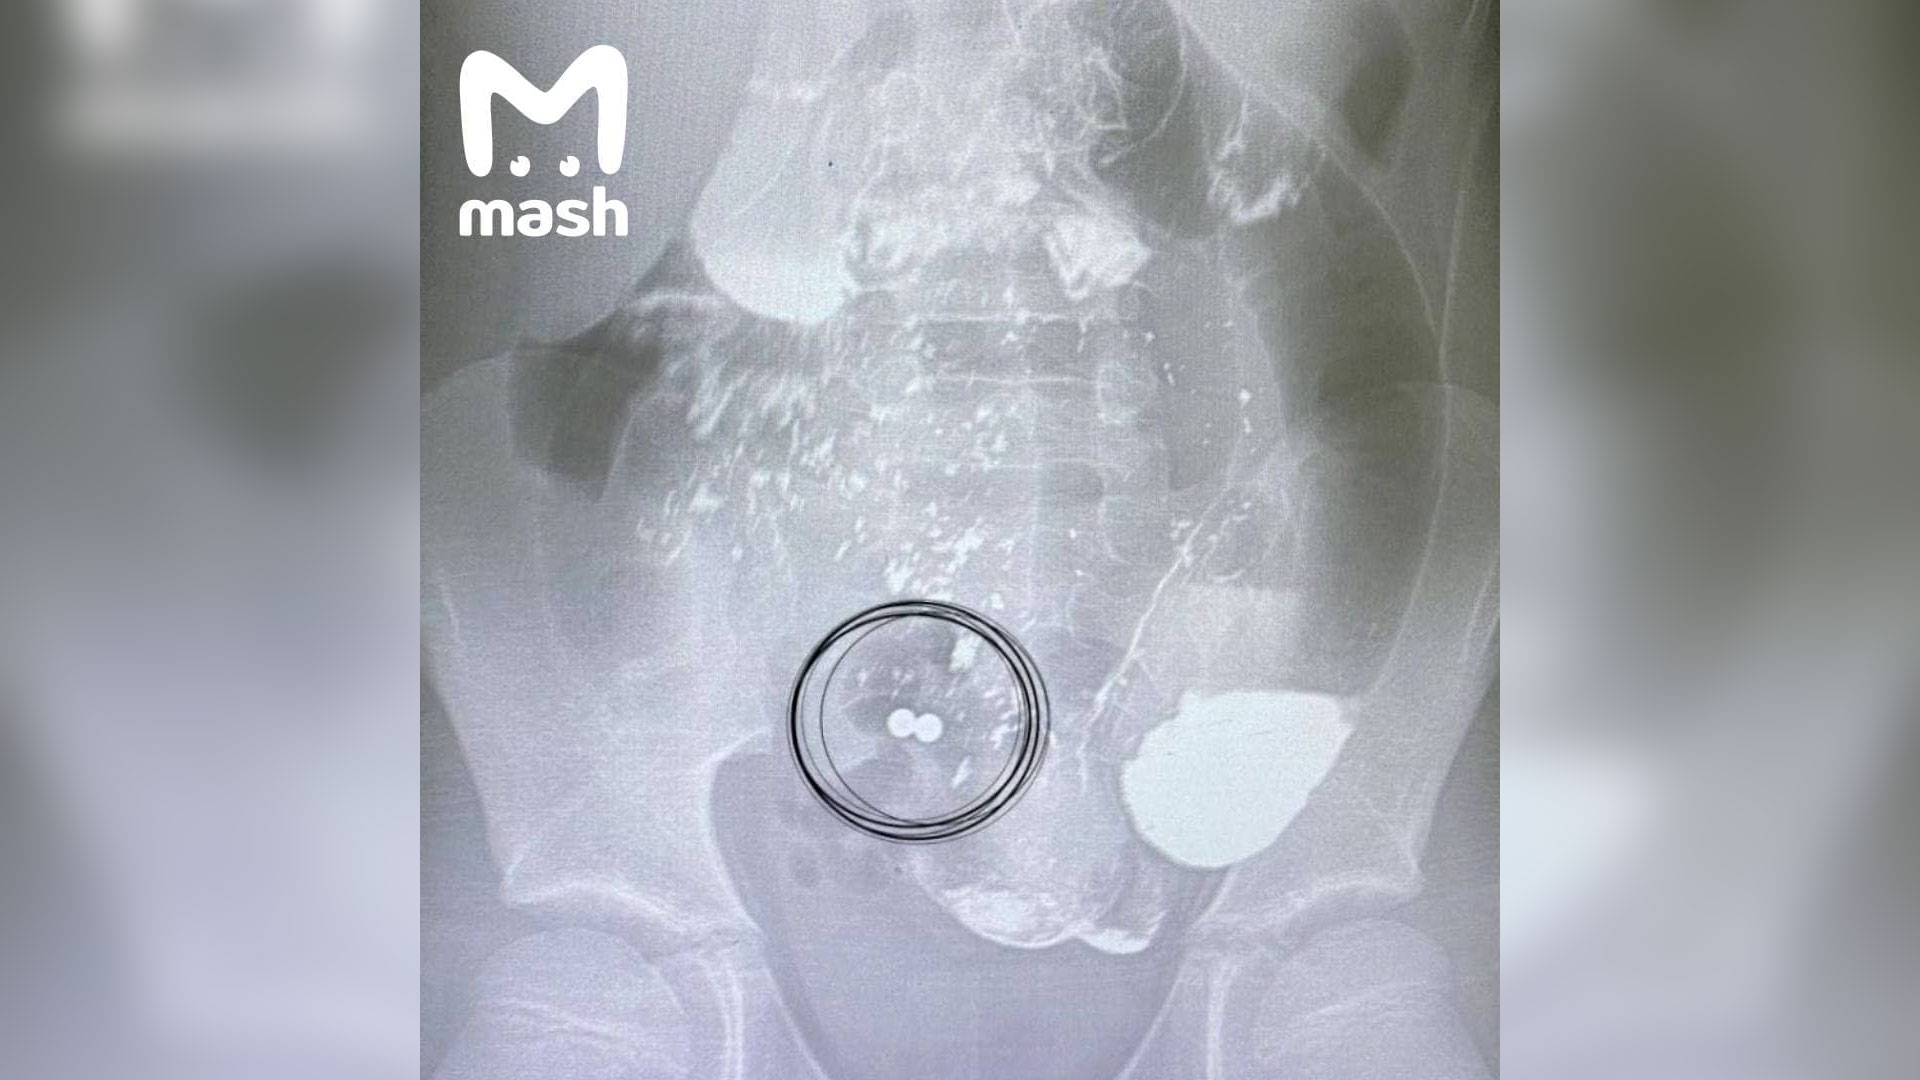

Магнитные шарики на рентгене: Интересные находки

Раздел: Картинки на заметку